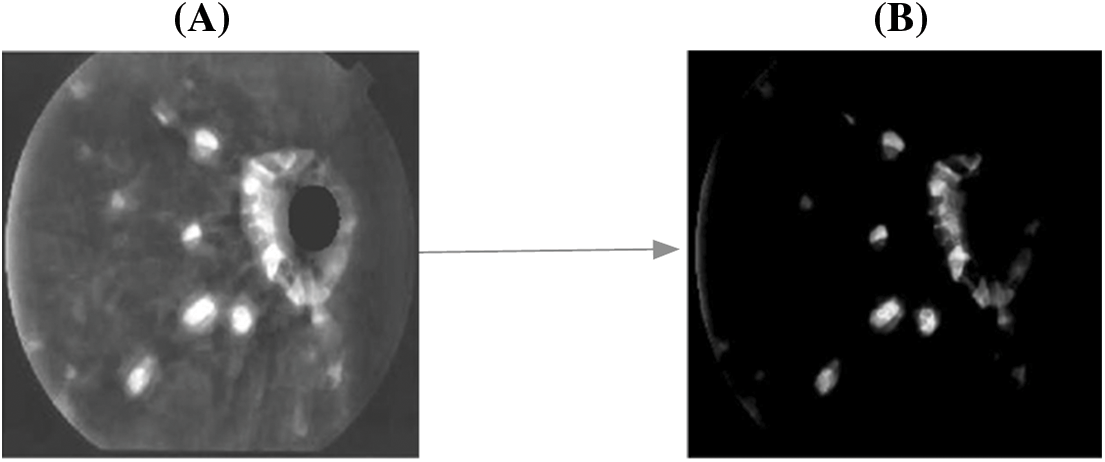

3.2.1 MCA Based Fundus Retinal Image Segmentation

The major idea of MCA is to process with the distinctive image structures and features. Using MCA, it is applicable to design a signal in linear mixture pattern contains many distinctive morphological elements. Moreover, the morphological components are featured with the redundant dictionaries, measures the result accuracy. The input fundus image is considered as FI0. FIA is the images with some region of blood vessels and FIB is the images without blood vessels. The steps for removing the blood vessels using morphological operations are presented below.

1. Here, ‘S’ denotes the structuring element that processes the image opening function

2. The vessels that are equivalent to ‘S’ are preserved and the others are discarded using,

where, ‘θ’ is the angle between the ‘S’ and blood vessels, ‘Len’ and ‘Wid’ are the length and width of the blood vessels, respectively.

3. Image opening function is performed in 12 different angular positions for enhancing accuracy and the equation is given as,

where, ‘Si’ is the factor of structuring element in ‘i'th angular position.

4. The same operation is performed for FIB and it is given as,

5. The equation of blood vessel separation is given as,

Fig. 4 depicts the corresponding findings after blood vessel elimination, and the steps for MCA-based object segmentation are detailed below.

1. The size of image FI0 is considered as M × M and it is converted into one dimensional vector as M2.

2. The one-dimensional vector is defined as a collection of ‘N’ different input features, which are denoted as,

where, ‘β’ is the image components and it is given as

3. Using the morphological component analysis, each element in ‘Ai’ can be obtained with the optimization issue with the condition, min‖θi‖.

4. Further, the value of ‘θi’ is given as thresholding rate obtained with the remaining marginal element, as in (14).

5. Here, all the elements, except the ‘i’ the element is fixed with the marginal remaining data of the element ‘Ai’.

Figure 4: A. FI with blood vessels B. FI without blood vessels

Based on the hard threshold rates, the process continues to obtain all ‘remi’ and the segmented object of the affected area from the fundus image is obtained. The corresponding sample figure is portrayed in Fig. 5.

Figure 5: A. Before segmentation B. After segmentation